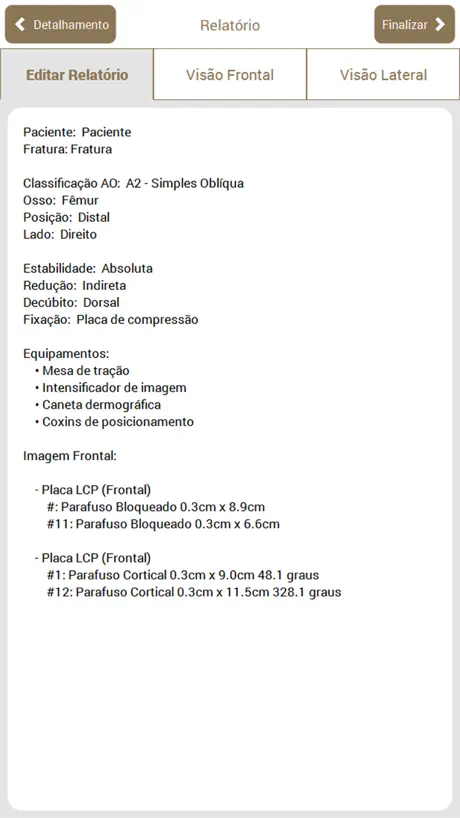

No aplicativo, é possível executar os mesmos passos que são feitos em um planejamento manual: Escolha da radiografia, Classificação AO, Seleção e recorte das partes, Redução, Planejamento dos Implantes, Preenchimento da ficha do paciente, Geração de relatório e Edição manual do relatório gerado (que pode ser exportado em PDF).

No aplicativo, é possível executar os mesmos passos que são feitos em um planejamento manual: Escolha da radiografia, Classificação AO, Seleção e recorte das partes, Redução, Planejamento dos Implantes, Preenchimento da ficha do paciente, Geração de relatório e Edição manual do relatório gerado (que pode ser exportado em PDF).